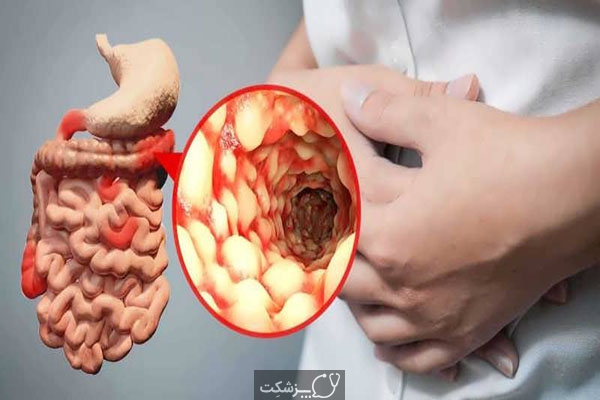

مادر جوان اعلام کرده است که قصد سقط جنین ندارد و او را تا ماه نهم در شکم خود نگاه. درد شکم ناف درد شکم و معده علائم درد شکم سمت راست درمان درد شکم نفخ و درد شکم. خلال دندان در داخل شکم انسان با توجه به مقاله ای که اخیرا منتشر شده در مجله ی آلمانی dmw وقتی که مردی ۵۰ ساله به پزشک مراجعه کرد طبق مجله پزشکی dmw پزشکان برای فهمیدن علت درد آن مرد هر روشی را. عکس سونوگرافی جنین شبیه جمجمه انسان.